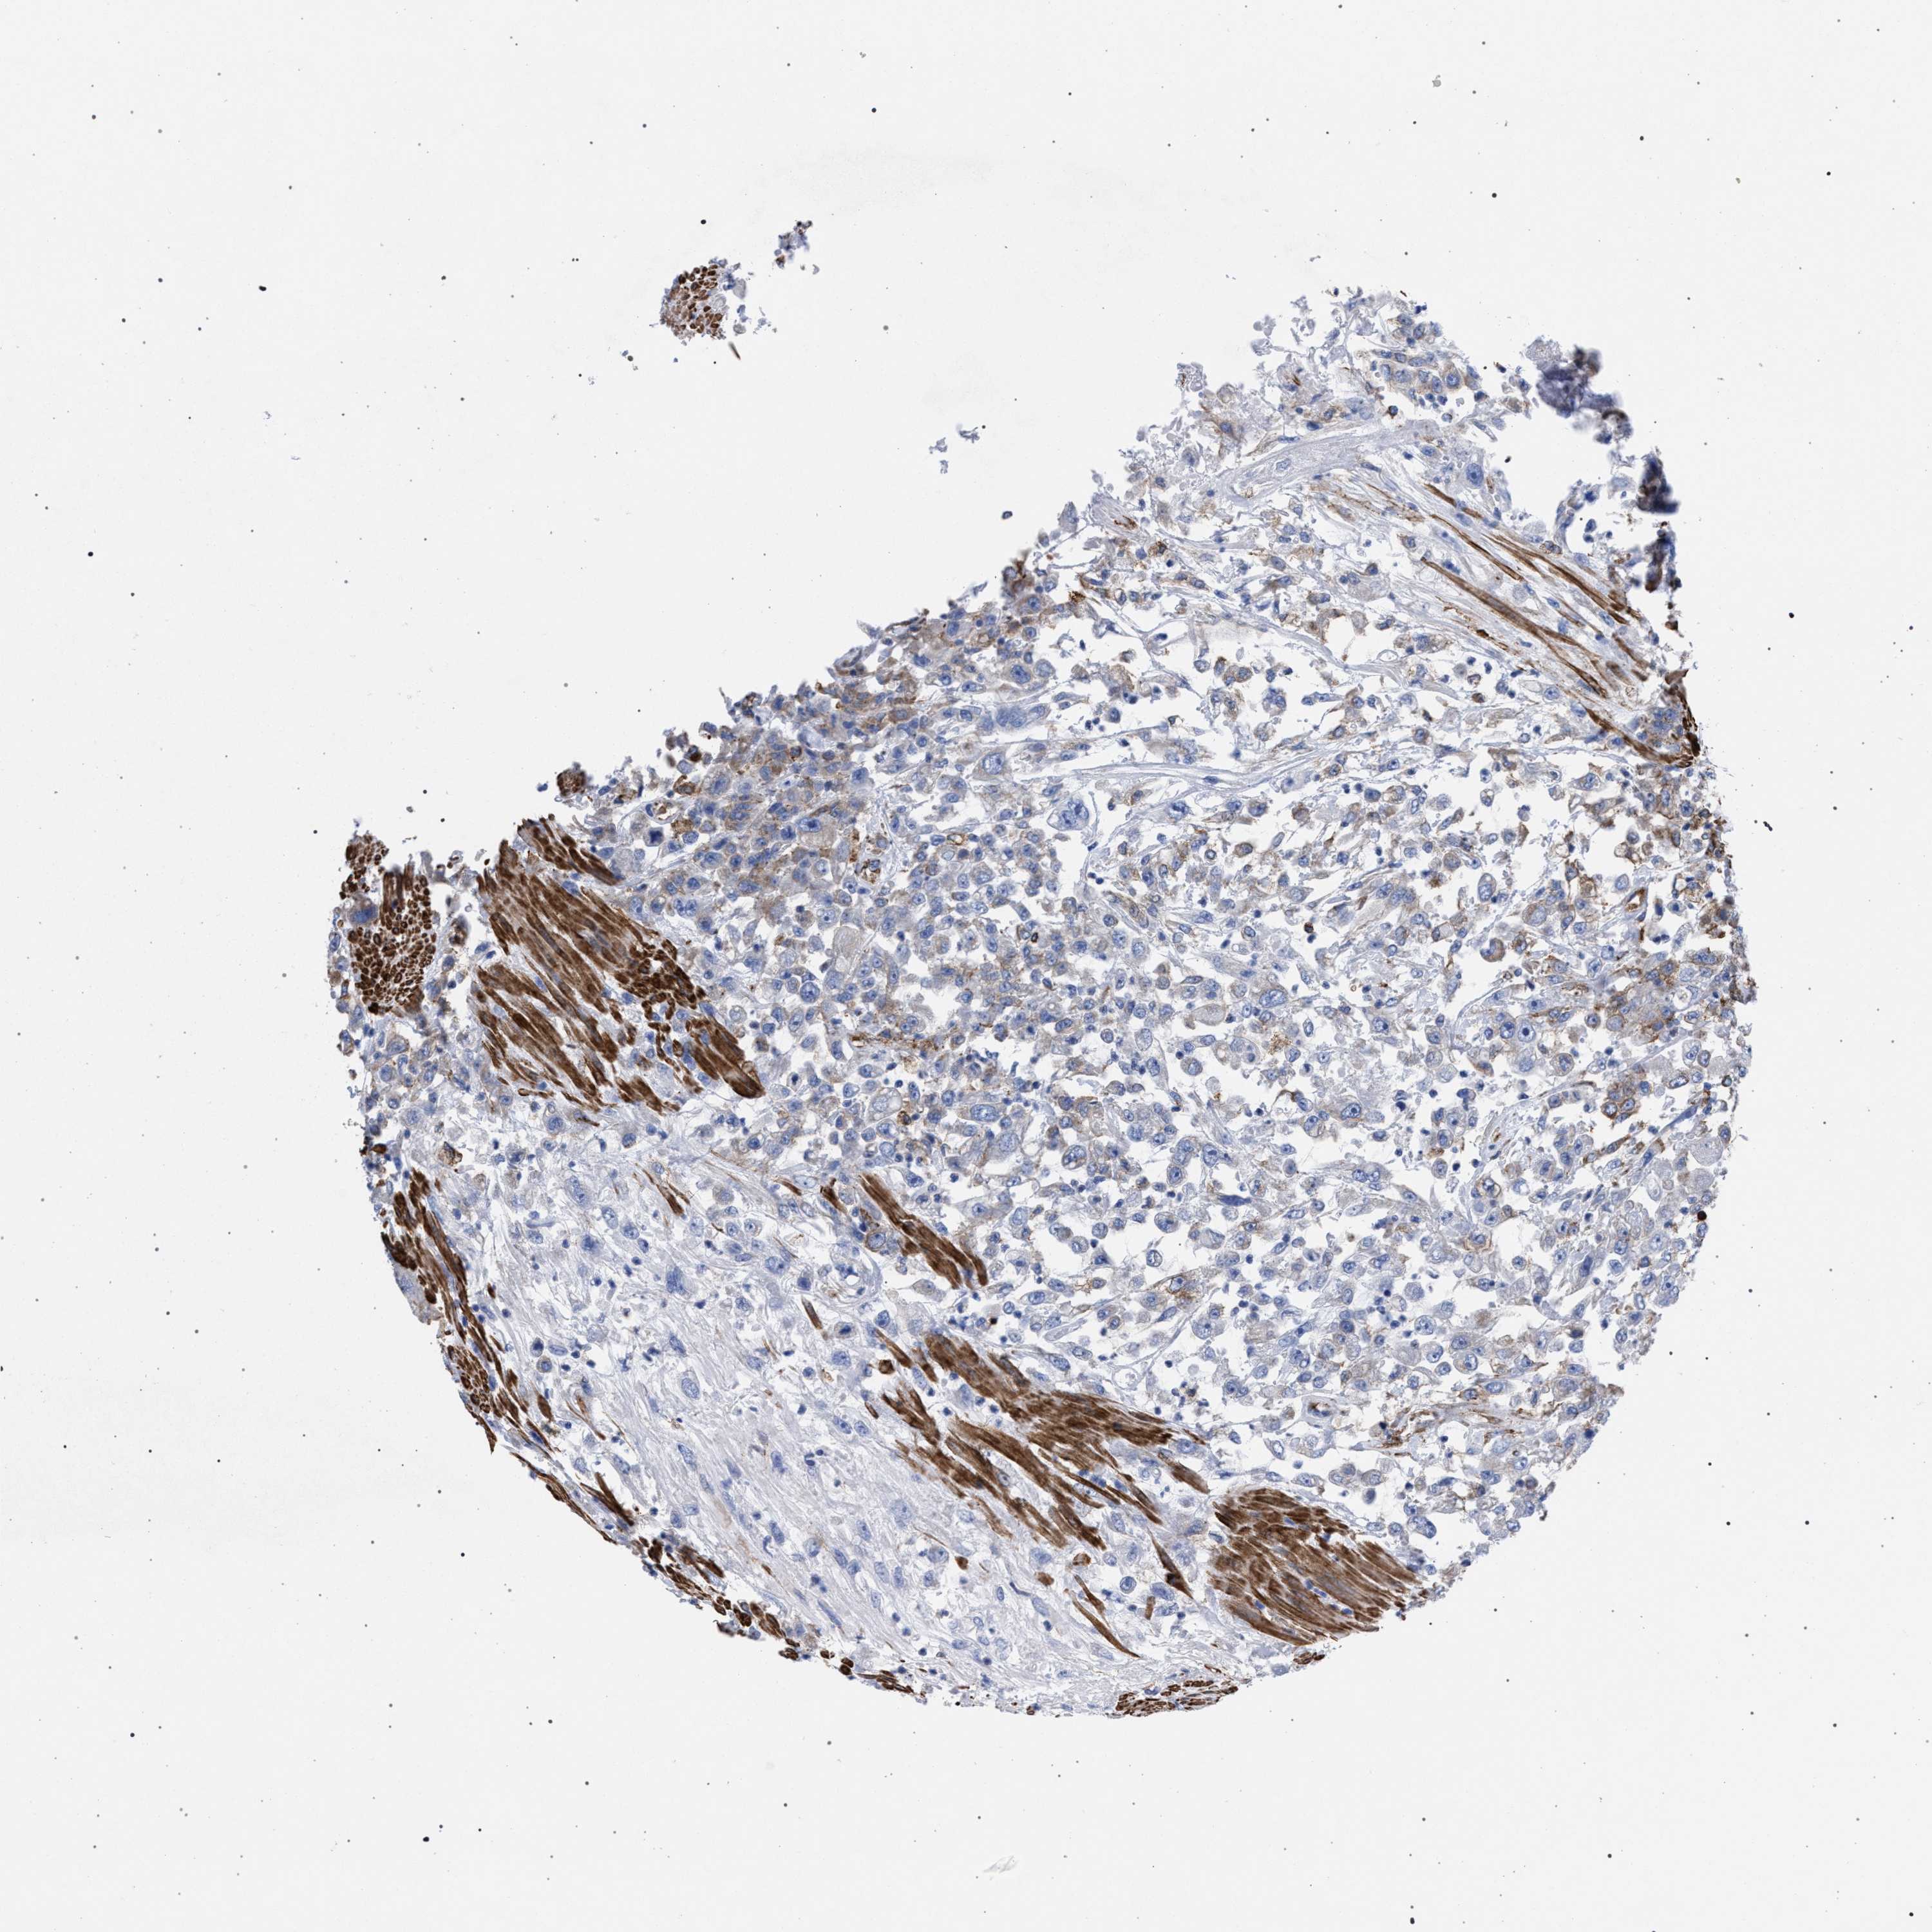

UROTHELIAL CANCER - Protein expressioni

A mouse-over function shows sample information and annotation data. Click on an image to view it in a full screen mode. Samples can be filtered based on level of antibody staining by selecting one or several of the following categories: high, medium, low and not detected. The assay and annotation is described here.

Antibody stainingi

Antibody staining in the annotated cell types in the current human tissue is reported as not detected, low, medium, or high, based on conventional immunohistochemistry profiling in selected tissues. This score is based on the combination of the staining intensity and fraction of stained cells.

Each image is clickable and will lead to virtual microscopy that enables deeper exploration of all samples and also displays staining intensity scores, fraction scores and subcellular localization as well as patient and tissue information for each sample.

Antibody HPA022271

Antibody CAB019284

Staining

High

Medium

Low

Not detected

Intensity

Strong

Moderate

Weak

Negative

Quantity

>75%

75%-25%

<25%

None

Location

Nuclear

Cytoplasmic/membranous

Cytoplasmic/membranous,nuclear

Urothelial carcinoma, Low grade

Urothelial carcinoma, High grade